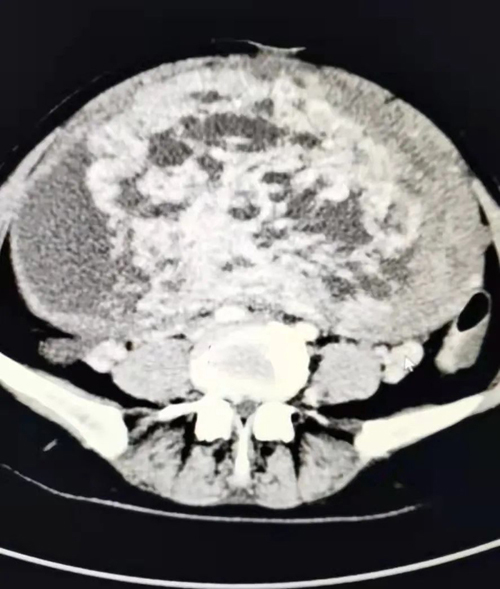

患者女,50歲,平素月經(jīng)規(guī)律,無痛經(jīng),無異常陰道流血,近半月來出現(xiàn)無明顯誘因腹脹、輕度腹疼、小便頻,來我院消化內(nèi)科就診,發(fā)現(xiàn)腹部異常膨隆,彩超見一巨大囊實(shí)性包塊,較大切面范圍約22.7*18.1CM,部分切面與宮底肌層關(guān)系密切,其內(nèi)囊性部分呈多房樣改變,實(shí)性部分血流信號豐富,CA125 98.85U/ml,以“盆腔包塊瘤”收入婦二科。

3月1日下午15:30分,患者被推進(jìn)手術(shù)室。按照術(shù)前制定的麻醉方案,麻醉醫(yī)師方軍為患者進(jìn)行了橈動脈穿刺和中心靜脈置管,實(shí)時(shí)監(jiān)測患者血壓變化,保證輸液通暢,確?;颊呤中g(shù)中生命體征平穩(wěn)。手術(shù)護(hù)士長安排了經(jīng)驗(yàn)豐富的護(hù)士甘瑾、邱靜靜和張兆霞配合手術(shù)。在麻醉科及手術(shù)室的支持配合下,手術(shù)有條不紊地進(jìn)行。打開腹腔后,見子宮異常膨隆,占據(jù)整個(gè)腹腔、盆腔,緩慢吸引出囊腔內(nèi)囊液約1500ml,將子宮搬出腹腔,沙袋壓迫上腹部,避免血壓驟降,手術(shù)歷經(jīng)2個(gè)小時(shí),完整切除了這一罕見的巨大肌瘤的子宮。術(shù)中快速病理為漿膜下平滑肌瘤,伴水腫囊性變。術(shù)后患者蘇醒,安返病房。